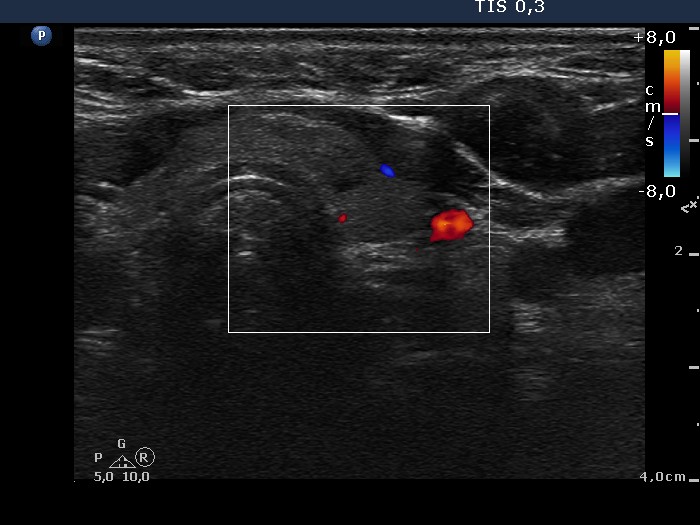

Left lobe, transverse view, color Doppler mode. The nodule is avascular.